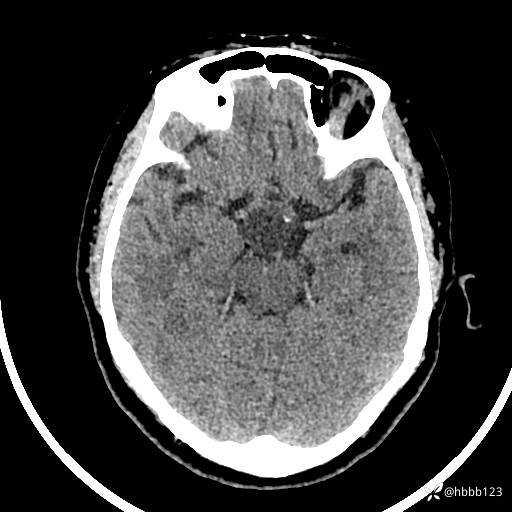

颅脑CT平扫: